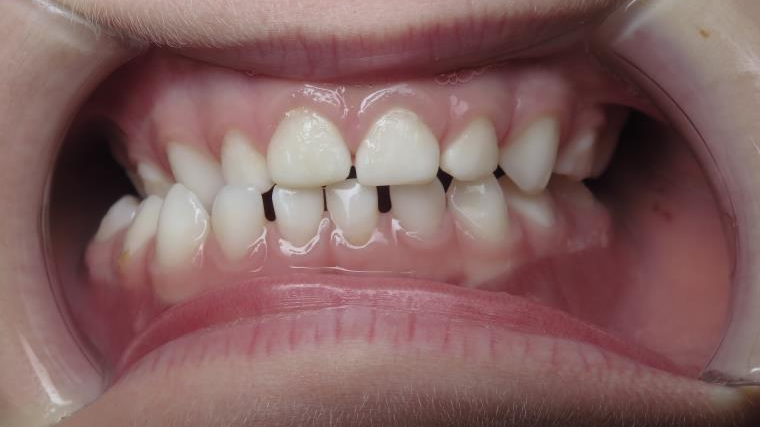

inversion des dents postérieur coté droit

appareillage mobile pendant 13 mois

bilan début et en cours de traitement